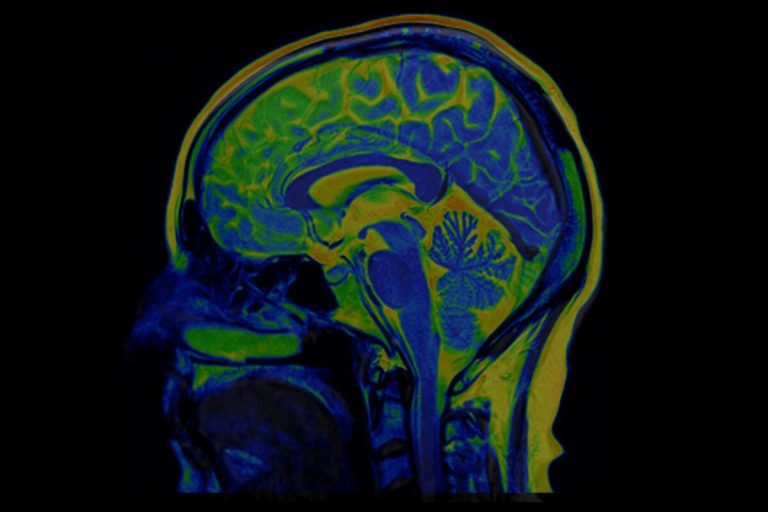

One of the first spectroscopic imaging-based studies of neurological injury in COVID-19 patients has been reported by researchers at Harvard-affiliated Massachusetts General Hospital (MGH) in the American Journal of Neuroradiology. Looking at six patients using a specialized magnetic resonance (MR) technique, they found that COVID-19 patients with neurological symptoms show some of the same metabolic disturbances in the brain as patients who have suffered oxygen deprivation (hypoxia) from other causes, but there are also notable differences.

The researchers used 3 Tesla Magnetic Resonance Spectroscopy (MRS), a specialized type of scanning that is sometimes called a virtual biopsy. MRS can identify neurochemical abnormalities even when structural imaging findings are normal. COVID-19 patients’ brains showed N-acetyl-aspartate (NAA) reduction, choline elevation, and myo-inositol elevation, similar to what is seen with these metabolites in other patients with white matter abnormalities (leukoencephalopathy) after hypoxia without COVID. One of the patients with COVID-19 who showed the most severe white matter damage (necrosis and cavitation) had particularly pronounced lactate elevation on MRS, which is another sign of brain damage from oxygen deprivation.

Compared to conventional structural MR imaging, “MRS can better characterize pathological processes, such as neuronal injury, inflammation, demyelination, and hypoxia,” adds Weerasekera. “Based on these findings, we believe it could be used as a disease and therapy monitoring tool.”